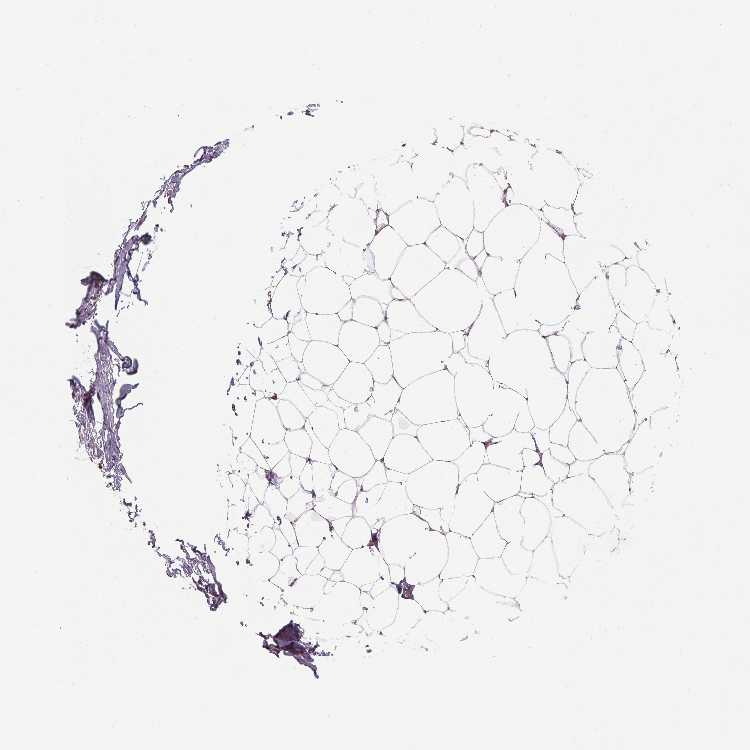

BREAST - Antibody stainingi

Antibody staining in the annotated cell types in the current human tissue is reported as not detected, low, medium, or high, based on conventional immunohistochemistry profiling in selected tissues. This score is based on the combination of the staining intensity and fraction of stained cells.

Each image is clickable and will lead to virtual microscopy that enables deeper exploration of all samples and also displays staining intensity scores, fraction scores and subcellular localization as well as patient and tissue information for each sample.

Antibody HPA068609

Adipocytes Low

Glandular cells High

Myoepithelial cells High